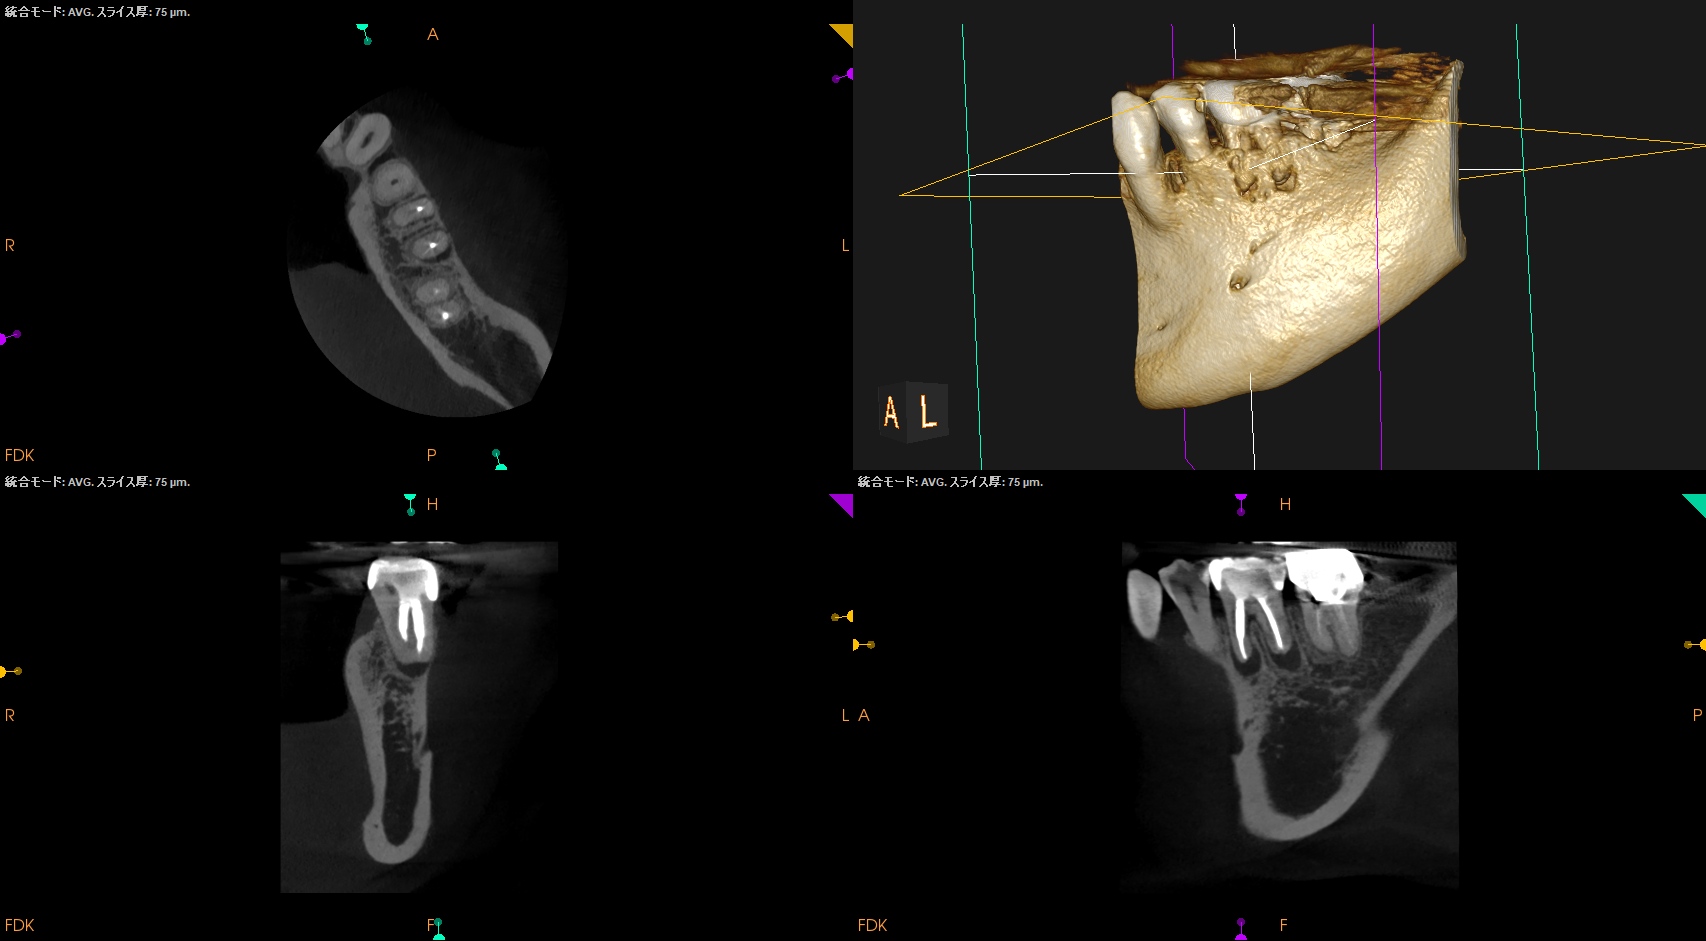

術後にPA, CBCTを撮影した。

MB

ML

D

B